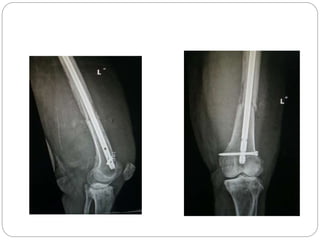

This document discusses 8 oncology cases. Case 1 involves a 40-year old female with right knee pain. Case 2 is a 28-year old male with a left subtrochantric fracture from a MVA who is now experiencing increasing left knee pain and swelling. Biopsy results showed high-grade osteosarcoma. Case 3 is a 30-year old female with breast cancer and bone metastases causing bilateral hip pain.